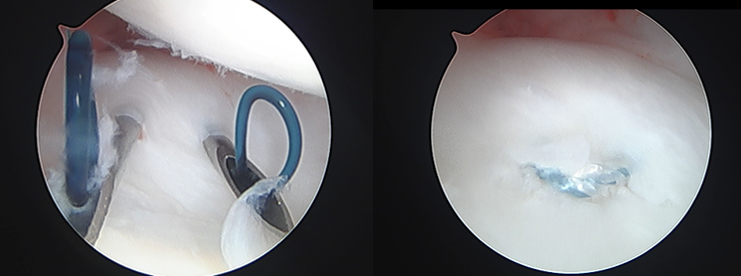

脱臼が生じると、骨、靭帯(関節包)が壊れます。そのまま放置すると壊れた部分がさらに大きくなることがあります。初期の段階では関節鏡により壊れた骨、靭帯を修復してくることが可能です(図1、2)。スポーツ選手の場合には早期復帰、復帰後の改善度を考えると重症化する前にしっかりと解剖学的に修復することが望ましいと考えます。特にラグビーやアメリカンフットボール、柔道、レスリング、アイスホッケーのような衝突を繰り返す可能性のあるスポーツにおいては十分な戦略を持った治療が満足する結果を出せると考えます。

これまで、スポーツによる肩関節障害は、様々な治療が試みられていますが、十分な成果を挙げているとは言い難く、肩の痛みによりスポーツを断念する選手は未だ数多く存在します。そもそも適切な診断がされていない場合が多いため、当院では、肩の痛みを診断から見直し、関節外における隠された神経症状(胸郭出口症候群や四辺形症候群など、胸郭出口症候群センターの項参照)、疲労骨折(図1)など、さらに関節内における関節唇(SLAP修復 図2)、関節包の損傷を把握することで、適切な治療を目指しています。スポーツ医学センター、リハビリ科とも連携して早期かつ元のレベルへの現場復帰をサポートします。

【図2 関節鏡によるSLAP修復(左肩を後方から見る)】

【関節鏡視下TFCC関節包縫合術】